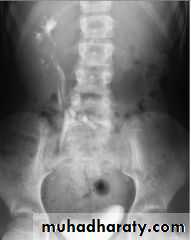

High density renal stonesStage horn calculus KUB filmsradio opaque stones

Failure of contrast to pass to ureters due to both sided mid ureteric stones

LT sided upper Ureteric stones

Bilateral HU + HN